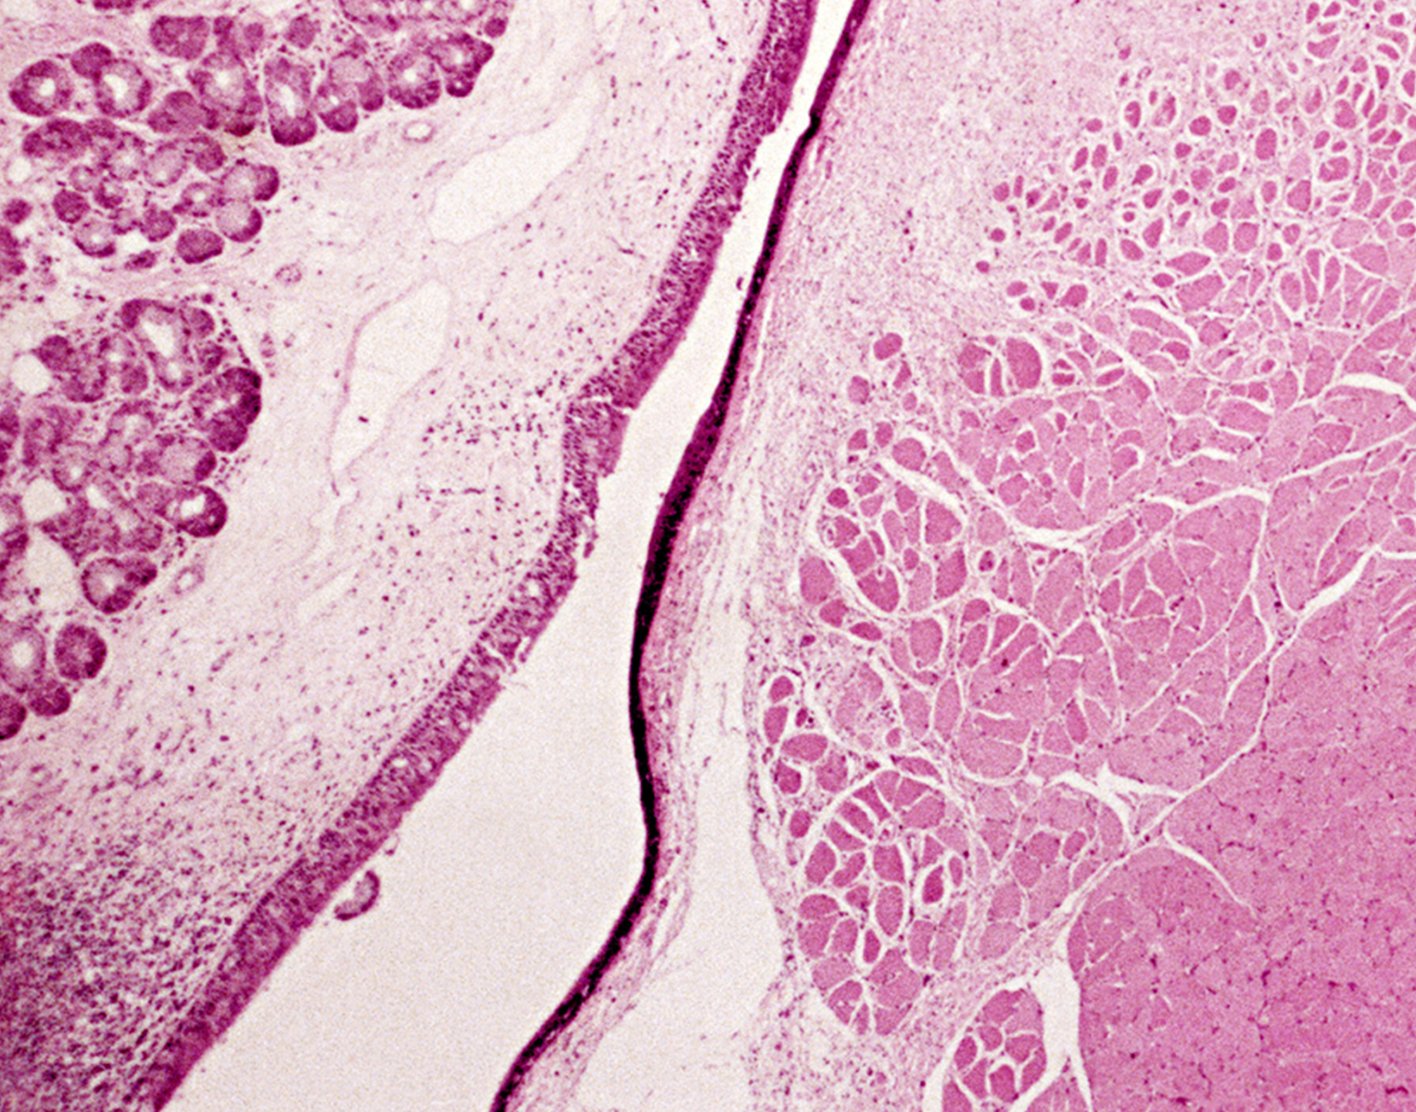

Laryngoscopy is an exam of the voice box (larynx). It can be done using a small mirror held just below the back of your palate, or a rigid or flexible viewing tube called a laryngoscope placed in your mouth.